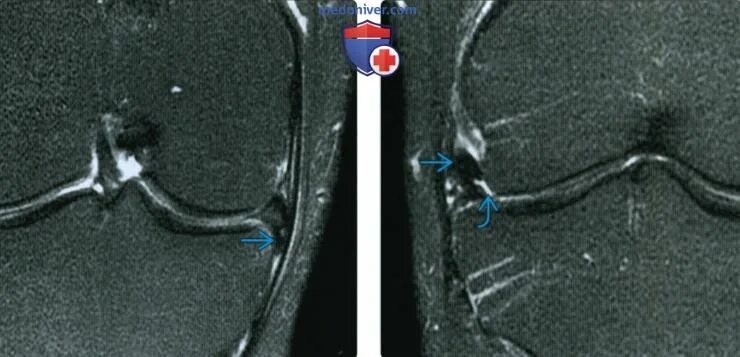

Повреждение мениска мрт